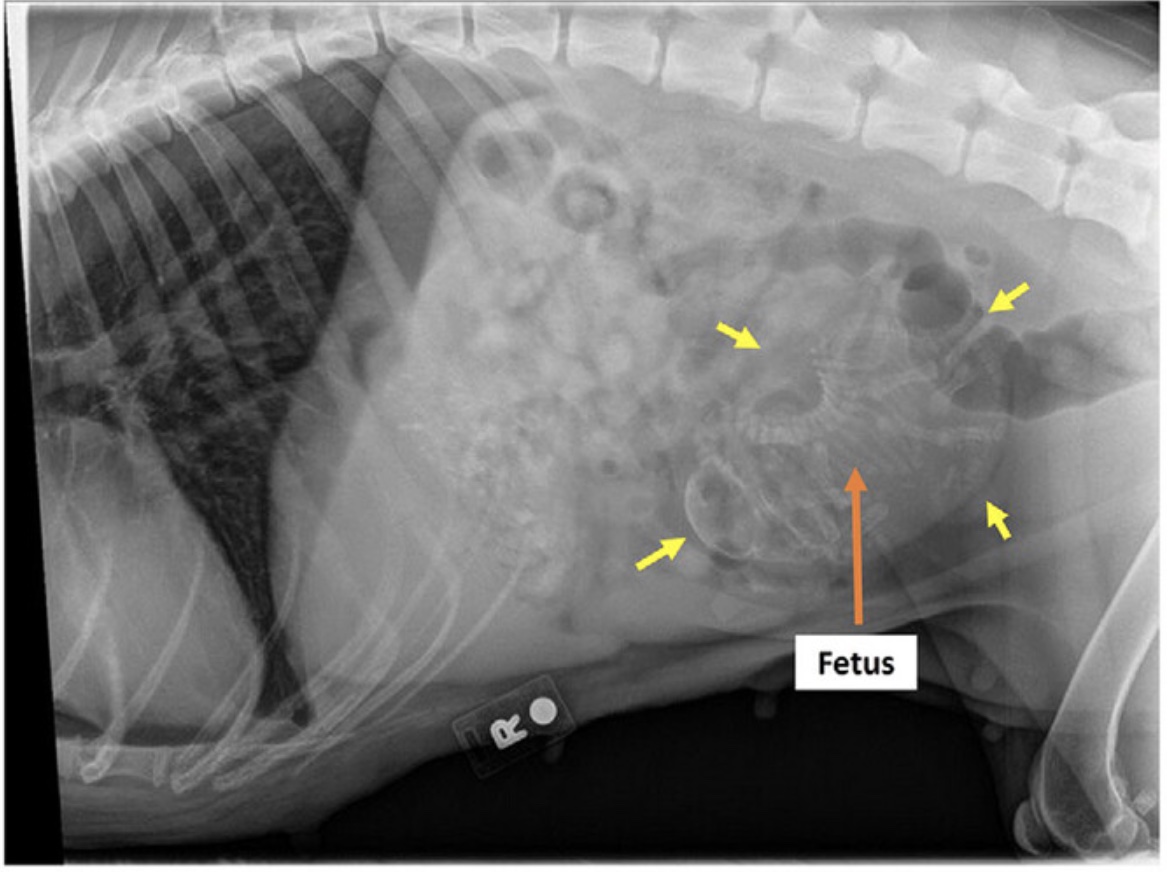

A full-term canine ectopic fetus in a post-caesarean patient

Lauren Natali; Veronica King; Ismael Concha; William Widmer